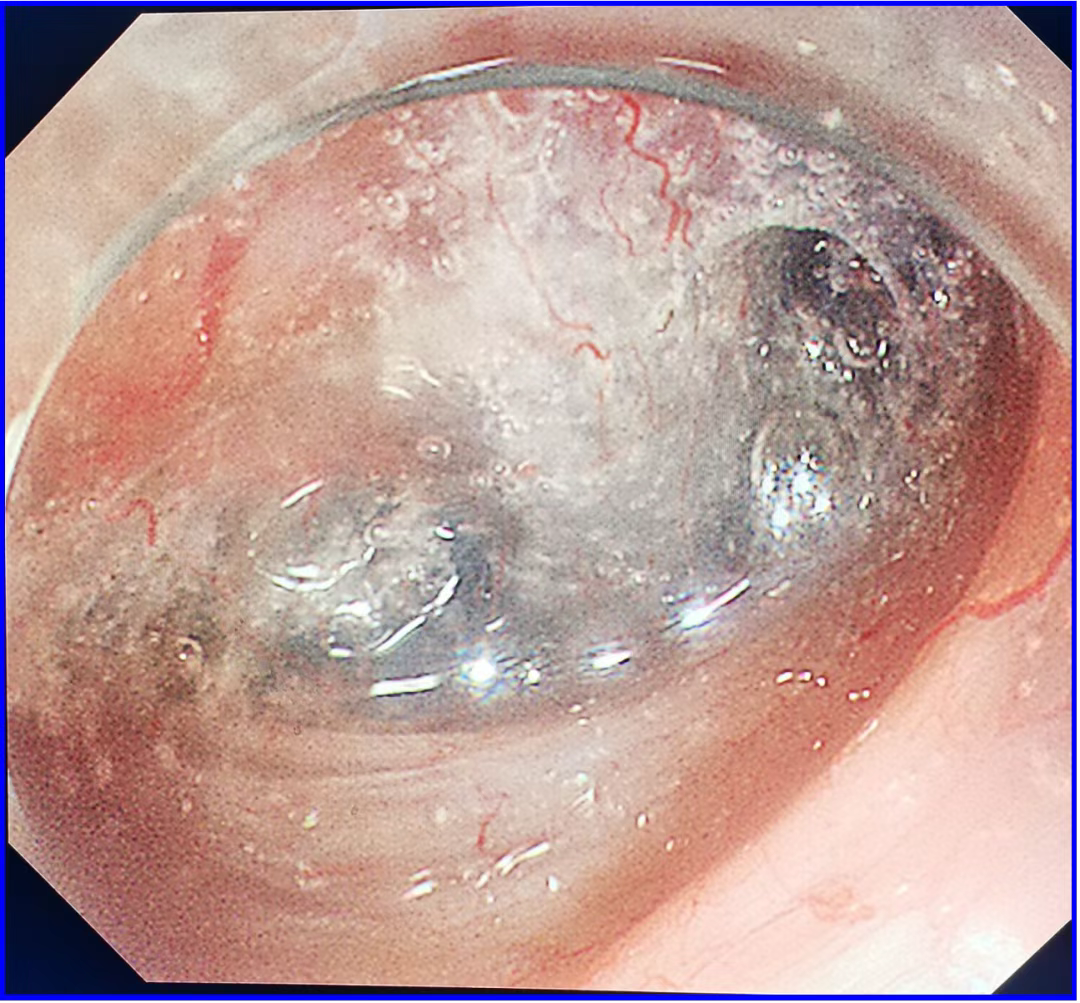

食管病灶

咽部病灶

1.(食管33处)食管糜烂型鳞状细胞癌,Ⅱ级,肿瘤大小0.6×0.3cm,癌组织局限于黏膜内(M2);淋巴管及血管内未见癌栓;送检组织四周及基底部切缘未见癌组织。免疫组化结果显示:CD34(未见癌栓),D2-40(未见癌栓),Desmin(平滑肌+),E-cadherin(+),Ki-67(index≈40%),P53(+,突变型)。

2.(下咽部)隆起型鳞状细胞癌,Ⅱ级,肿瘤大小1.8x1.2,癌组织侵及黏膜固有层;淋巴管及血管内未见癌栓;切缘及基底部切缘未见癌组织,(肿物距基底部切缘约200微米)。免疫组化结果显示:CD34(未见癌栓),C-erbB-2(1+),CK5/6(+),D2-40(未见癌栓),EGFR(+)、Ki-67(index≈50%),P53(-),P63(+)。

根据患者术后病检,患者达到临床治愈,无需放化疗,只需定期复查,真正做到了早发现、早治疗。